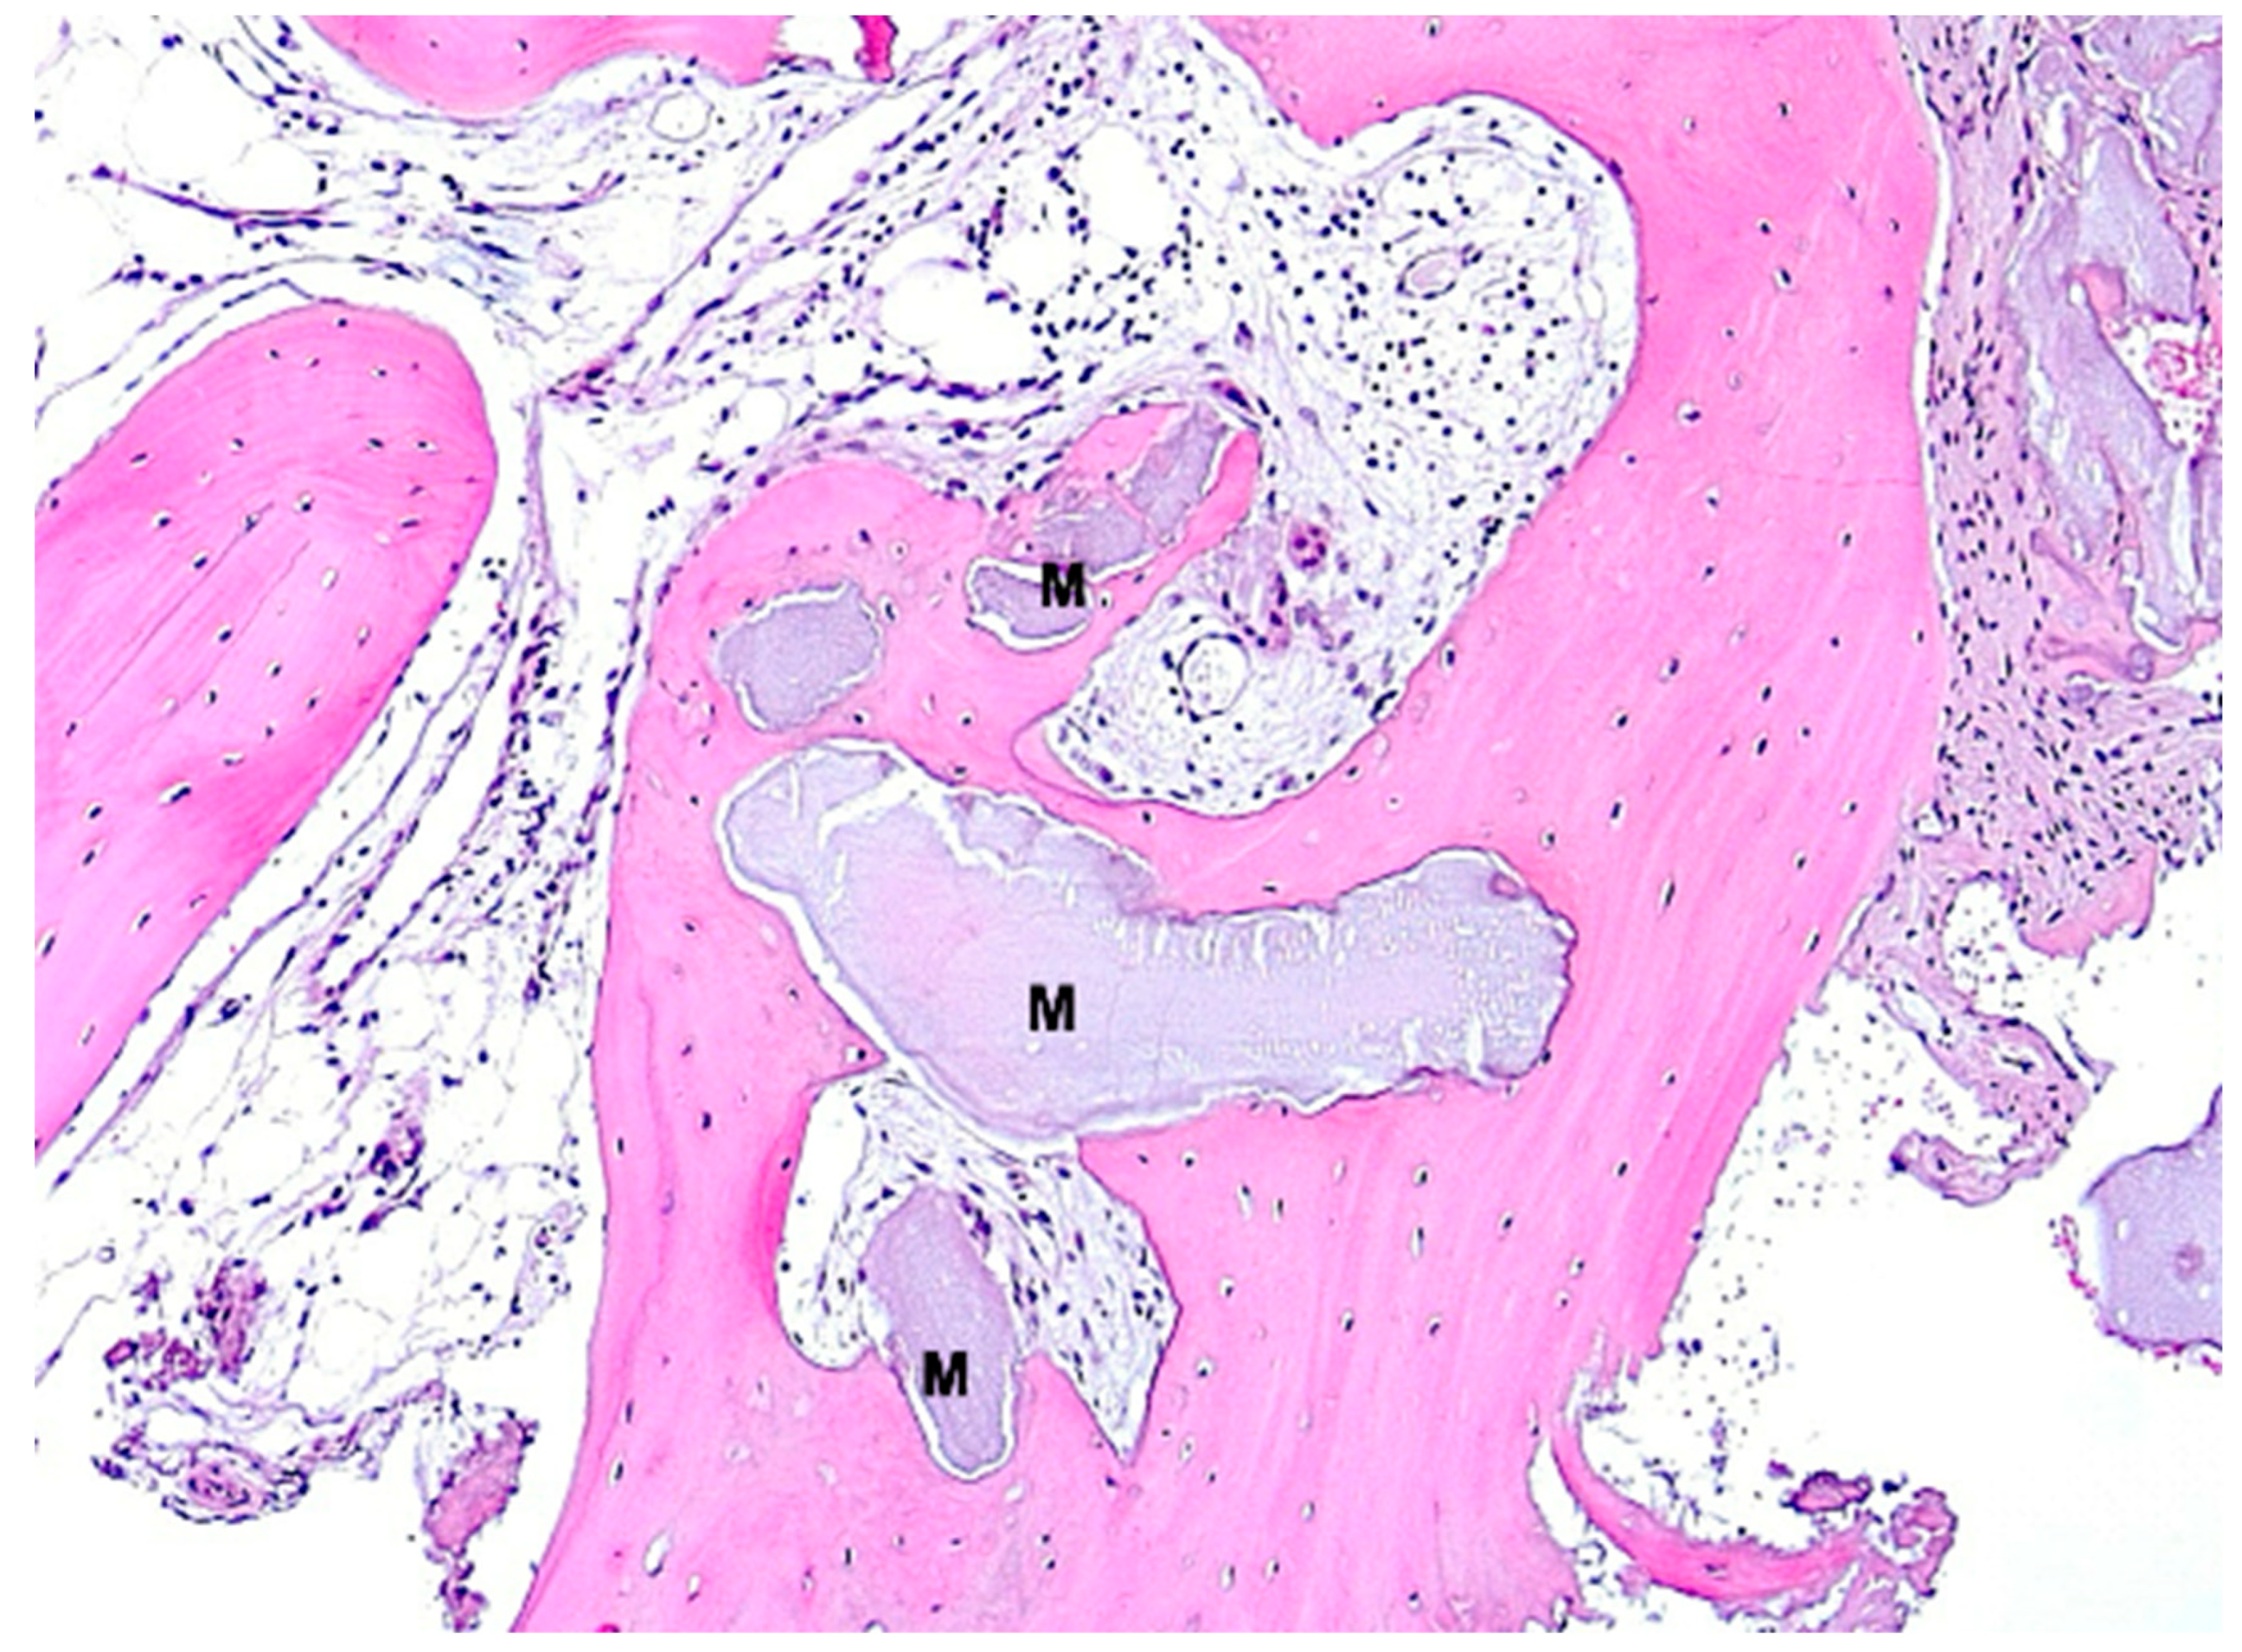

Under low magnification, most biopsies appeared as cylindrical specimens primarily composed of cancellous bone, featuring interconnected trabeculae of varying diameters, MinerOssX (MOX) granules with active osteogenesis, and intertrabecular connective tissue (Figure 8, Figure 9 and Figure 10). Areas of osteogenesis were mainly localized to the more coronal parts of the biopsies (Figure 8). Artificial ecchymosis and fragmentation of bone or connective tissue due to trephination were evident in nearly all the specimens. The basophilic MOX granules varied in size and shape, showing signs of degradation (Figure 9, Figure 10, Figure 11 and Figure 12). All the biopsies exhibited a network of cancellous bony trabeculae formed through appositional membranous osteogenesis at various stages around MOX granules or larger spongy or compact ossicles with minor granule remnants (Figure 9 and Figure 10). Newly formed bone was fibrous (Figure 9 and Figure 10). The early stages of perigranular osteogenesis were marked by the ingrowth of connective tissue into granules and the formation of osteoids around them (Figure 11). However, nearly all the specimens contained MOX granules without signs of osteogenesis, most displaying a thin, peripheral, dark basophilic layer (Figure 12). In some instances, this layer was visible as an interface between the granules and newly formed bone. Some surfaces of newly formed bone were covered by osteoblasts (Figure 13). In some specimens, the fibrous bone had already remodeled into mature cancellous or compact bone, appearing as lamellar bone with incorporated fibrous bone remnants (Figure 13). The bone surfaces were mostly covered by lining cells. The intertrabecular tissue consisted of loose or fibrous connective tissue with fibroblasts and moderate vascularization (Figure 10, Figure 11 and Figure 12). Osteoclasts were present on the surfaces of the newly formed bone and MOX granules (Figure 13). No foreign body giant cells were detected. Small, loosely arranged infiltrations were observed in three specimens (Figure 14). Necrosis was not observed. TRAP-positive osteoclasts were found on the surfaces of MOX granules without osteogenesis or bone deposition (Figure 15). COL I immunostaining showed weak to moderate staining in the matrix of newly formed bone, with stronger staining in osteoid seams and osteocytes. Focal immunoreactivity was observed in osteoblasts (Figure 16). Additionally, connective tissue staining was present. COL I exhibited weak to moderate staining intensity in the granule matrix and their interfaces (Figure 16). The newly formed bone matrix showed weak OC immunostaining, with most osteoblasts, osteocytes, and some fibroblasts near the bone surfaces staining more intensely (Figure 17). The interfaces between the MOX particles and newly formed bone and granule matrix were also reactive. Staining for vWF indicated moderate to good vessel density in most specimens, with capillaries, small arterioles, and large sinusoids being the predominant vessel types located between the bone trabeculae and granules (Figure 18). There was no clear correlation between the progression of osteogenesis and the duration of bone substitute placement. In patients with diabetes and atopy, osteogenesis was poorly developed.

Figure 10.

Biopsy case 8, advanced osteogenesis around bone graft granule remnants (M), HE, original magnification ×10.